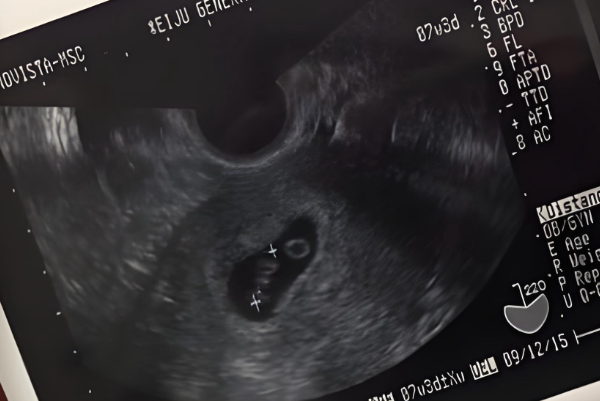

COUTACT US试管怀孕到了11周,做B超检查时没看到胎心这种情况正常与否还需要结合实际孕周来判断,因为试管怀孕的孕周计算有时候会和自然怀孕不太一样,如果孕周算错了,可能胎心还没到该出现的时候,另外,每个人的身体状况不同,胚胎发育速度也会有差异,所以遇到这种情况,先冷静下来,仔细核对一下孕周,看看是不是计算有误,然后再考虑其他因素。

如果孕周计算正确,但11周了还是没见到胎心,这背后其实有好几种可能性,当然,最终还是要通过专业检查来确认,但心里有个底总归是好的。具体如下所示:

1、孕周计算出了岔子:试管怀孕的孕周计算有时候会搞混,比如从移植日算起,或者根据取卵日来推,但如果记错了日期,或者月经周期不规律,就可能把实际孕周算小了。这样一来,胎心可能还没到该出现的时候,自然在B超上看不到。很多人容易忽略这个细节,总觉得日子没错,结果白担心一场;

2、胚胎发育慢了半拍:有些胚胎天生发育就慢点,不像别人家孩子那样按部就班。正常情况下,胎心在6到8周左右出现,但个体差异大,有的可能拖到10周甚至更晚。如果准妈妈身体状态不太好,或者营养没跟上,胚胎可能长得慢吞吞的,胎心自然就晚点露面。这不代表一定有问题,只是需要多点耐心等等;

3、胚胎已经停止发育:这是比较让人难受的可能性,就是胚胎在早期就停止生长了,可能因为染色体异常或者其他内在问题。一旦停育,胎心就不会出现,B超检查也只能看到空囊或者没有活力的迹象。这种情况在试管中不算少见,毕竟辅助生殖技术本身就有一定风险,需要理性面对;

4、检查设备或操作有误差:B超检查不是百分百精准,有时候设备老旧,或者操作人员经验不足,可能没扫到胎心的位置。另外,如果准妈妈肚子脂肪厚,或者憋尿不够,图像不清晰,也容易误判。所以一次检查没看到胎心,别立马灰心,复查一下说不定就有转机。